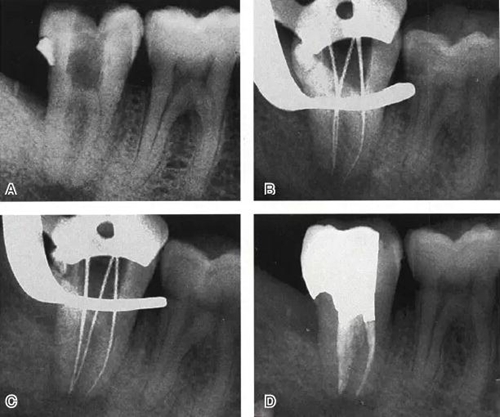

圖6 Ⅱ型C形根管治療典型病例,A:初尖銼片,B:主尖銼片,C:根充片,D:術(shù)后片

圖7 Ⅲ型C形根管治療典型病例,A:初始片,B:初尖銼片,C:主尖銼片,D:充填片